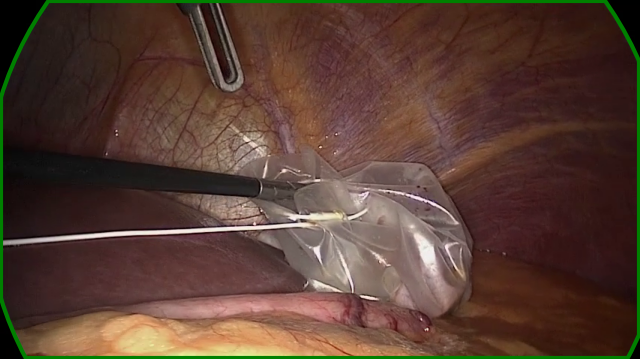

Refer to caption

(a) The dark right-hand side of the content area is missed by both variants. The learned variant gets a slightly better fit, this could be due to a better positioing of points on the left-hand side of the content area.

(b) A noisy and bright border poses a challenge for the handcrafted variant. Too few edge points are detected to make a confident estimate of the circle. The learned variant manages to correctly identify the right-hand edge of the content area, however, the circle fits to incorrect edge points found on the blacked out secondary video feed in the top-left.

(c) Both variants correctly identify the edge in the bottom-left but mistake dark regions in the top-right and bottom-right corners as border regions. The learned variant rejects the final circle as the circle score is too low. This scenario, where a single corner of the image is outside the content area, features prominantly in our failure cases.

(d) In this sample, the handcrafted variant detects edge points in the bottom-left, but scores them poorly. The circle fitting then chooses the incorrectly identified edge points in the top-left. The learned variant scores the detected points in the bottom-left higher, and so the circle fitting finds a satisfying result.

Figure 6: A selection of failure cases of our algorithm taken from the RobustECA dataset, the results of both the handcrafted (left) and learned (right) variants are shown for each image. The edge of the ground truth and inferred circular image projections are shown in blue, and green, respectively. Points indicate the position of detected edge points, the colour of each point indicates its score, going from red to green as the score increases. The vector found when calculating the Hausdorff distance is shown in yellow.